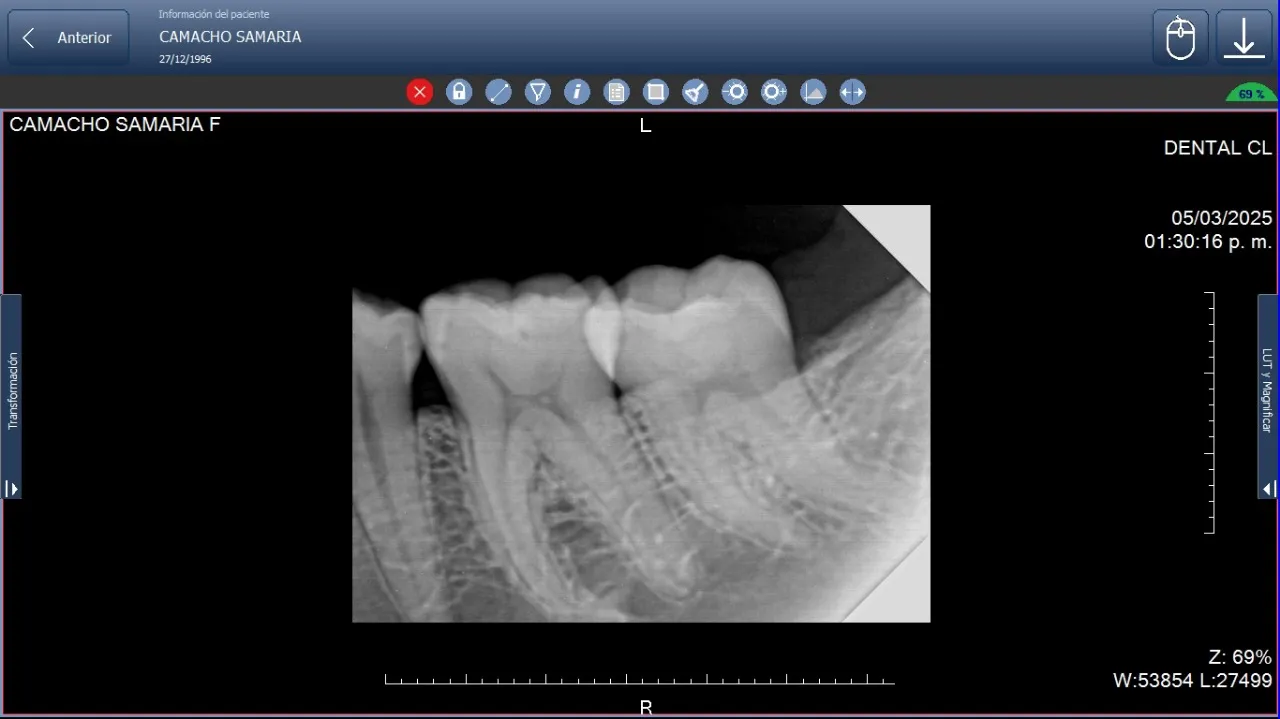

El uso adecuado de los equipos de rayos X dentales periapicales, especializados en radiografías periapicales, se ha consolidado como una herramienta indispensable en la práctica odontológica y en la odontología veterinaria. Estos dispositivos permiten obtener imágenes diagnósticas de alta precisión de dientes,